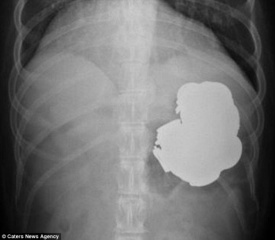

Ao longo de um período de três anos, Rajpal Singh, de 34 anos, engoliu 140 moedas, 150 pregos e um punhado de porcas, parafusos e baterias. Ele também já engoliu pregos e ímãs. Quando os médicos realizaram uma endoscopia – a inserção de um longo e fino tubo com uma câmera acoplada – as centenas de objetos estranhos em seu estômago foram revelados.

Gagandeep Goyal, gastroenterologista do hospital local que desvendou os corpos estranhos no estômago de Singh, realizou 240 procedimentos para remover os objetos, e mesmo assim, alguns permaneceram no local.

Liderando uma equipe de cinco médicos, ele também realizou uma operação de nove horas para remover o resto do metal. Singh ainda vai precisar de outra operação para remover o que ainda falta. “O paciente veio até nós com fortes dores de estômago. Quando fizemos a endoscopia, ficamos chocados ao ver tantos corpos estranhos, inclusive moedas e objetos pontiagudos em seu estômago. Embora tenhamos conseguido remover a maioria deles, há ainda objetos afiados e moedas em seu estômago”, disse Goyal.